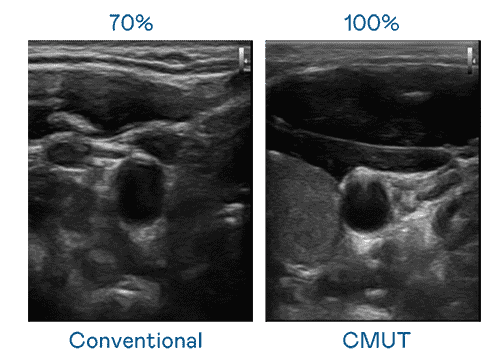

CMUT 技术是一种用电容式微机电元件来产生超音波讯号的技术。。。。与传统 PZT 压电式技术相比,,CMUT 频宽增加 30%,,,更宽频的超音波讯号让影像解析度大幅提升,,,是实现高影像品质医疗超音波扫描、、、促进精准医疗发展的关键技术。。。。

大频宽带来超清晰影像

超音波影像的解析度高低,,,,首先取决于探头能发出的讯号频宽。。红龙扑克 CMUT 可提供高清晰的超音波讯号,,,,提供高频宽、、、、高灵敏度、、、、影像纹理细节更高的超音波影像,,,协助医护人员缩短影像判读时间及利用精准的医疗影像进行诊断。。